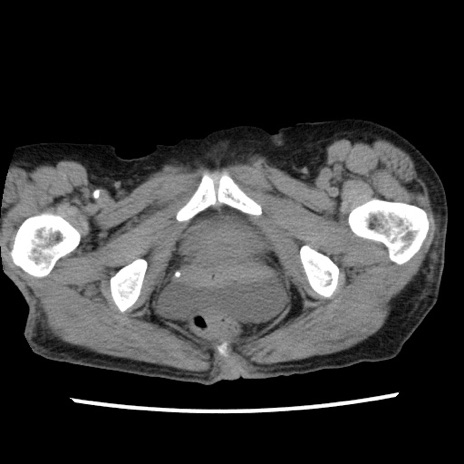

矢状断像